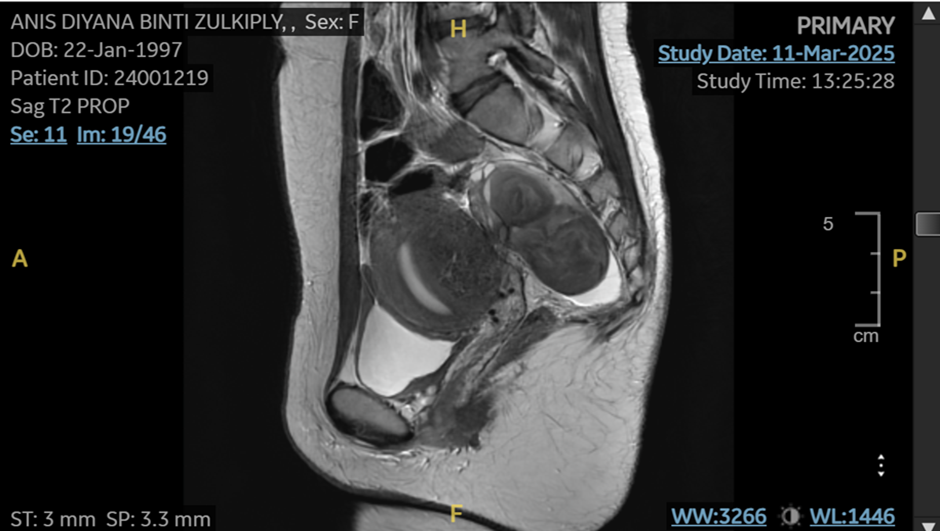

2) Ultrasound / MRI

Ultrasound of pelvis or MRI to diagnose and map the endometriosis are both equally accurate and useful. Specialised imaging can detect:

- endometriomas (chocolate cyst)

- the location of deep infiltrating endometriosis

- adenomyosis or fibroids

- pelvic adhesions and organ fixation

However, imaging requires both experience and the right technique. Not all general gynaecologists are trained in ultrasound to detect endometriosis, and not all radiologists are trained to interpret endometriosis accurately on MRI.